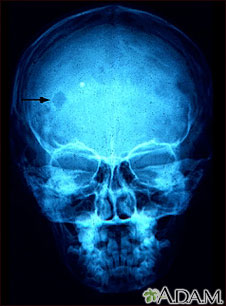

Esta radiografía de cráneo muestra un granuloma eosinofílico, que es una lesión compuesta por un tipo de glóbulos blancos. La gravedad de esta condición puede variar desde una lesión única hasta la infiltración masiva de la piel, el hueso y los órganos corporales.